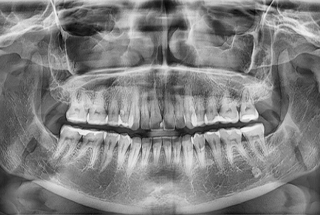

CBCT stands for Cone-beam (or Conebeam) Computed Tomography. It takes highly detailed, three-dimensional images that provide much more information than a standard digital X-Ray. For example, instead of just producing images of the bones and teeth, it also shows nerves and connective tissues.

A CBCT machine can play a pivotal role in helping your dentist in McKinney diagnose complex dental problems and plan for advanced procedures. These machines are commonly used in the planning process for root canal therapy and dental implant placement surgery. The Vatech PaX-i 3D comes with special software that makes the treatment planning process even easier.